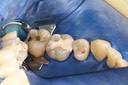

Wayne Chin #14 prep